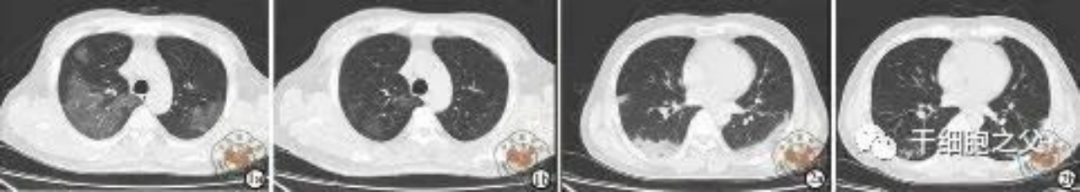

如圖所示,1a-1b:細(xì)胞輸注后,炎癥指標(biāo)改善,復(fù)查胸部CT提示雙肺病灶較前吸收,呼吸道癥狀改善,新型冠狀病毒核酸檢測(cè)連續(xù)2次陰性,治愈出院。圖2a-2b:2次干細(xì)胞輸注后炎癥指標(biāo)改善,復(fù)查時(shí)氧合指數(shù)升高至301 mmHg,胸部CT提示雙肺病灶較前吸收,患者呼吸道癥狀改善,新型冠狀病毒核酸檢測(cè)連續(xù)2次陰性,治愈出院。